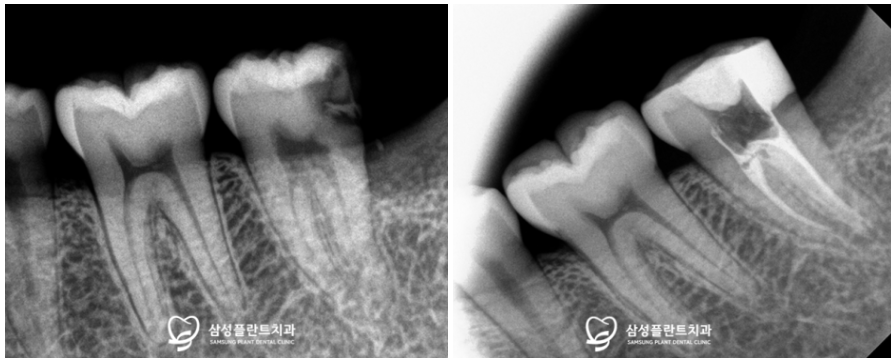

신정네거리역치과

더불어 사랑니를 발치하고 나서

왼쪽 아래 어금니는

신경치료를 깔끔하게 진행했습니다.